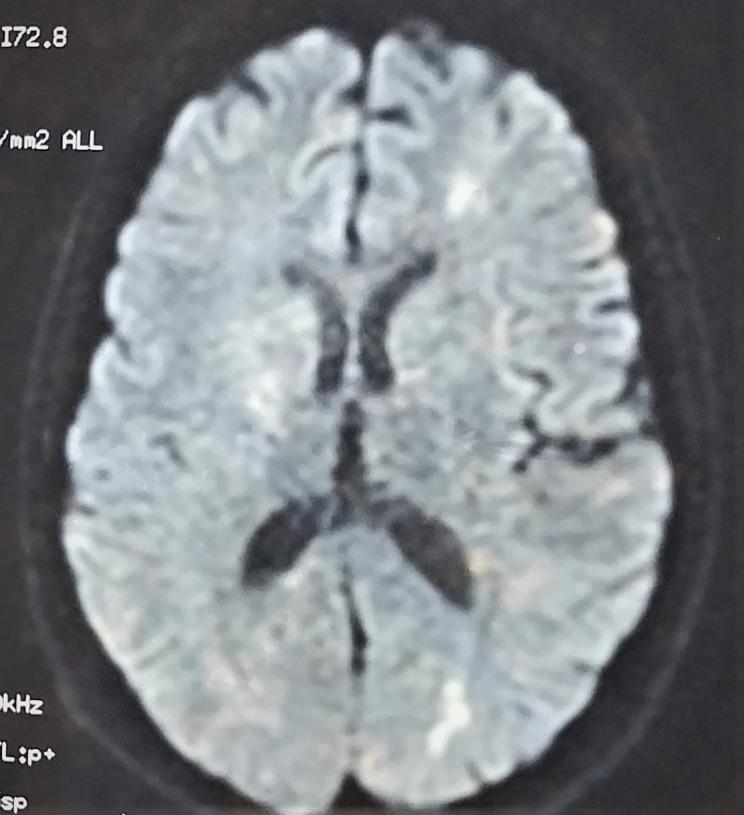

A 26-years old female with a family history of a mother diagnosed with schizophrenia, and no personal medical or psychiatric history, was diagnosed with mild COVID-19 infection four days after receiving the second dose of Pfizer-BioNTech COVID-19 vaccine. One month after receiving the vaccine, she presented to the psychiatric emergency department with acute psychomotor agitation, incoherent speech and total insomnia evolving for five days. She was firstly diagnosed with a brief psychotic disorder according to the DSM-5, and was prescribed risperidone (2 mg/day). On the seventh day of admission, she reported the onset of severe asthenia with dysphagia. Physical examination found fever, tachycardia, and multiple mouth ulcers. Neurological evaluation revealed a dysarthria with left hemiparesis. On laboratory tests, she had severe acute kidney failure, proteinuria, high CRP values, and pancytopenia. Immune tests identified the presence of antinuclear antibodies. Brain magnetic resonance imaging (MRI) revealed hyperintense signals in the left fronto-parietal lobes and the cerebellum. The patient was diagnosed with systemic lupus erythematosus (SLE) and put on anti-SLE drugs and antipsychotics, with a favorable evolution.

一名 26 岁女性,有一位被诊断患有精神分裂症的母亲,无个人医疗或精神病史,在接种辉瑞-BioNTech COVID-19 疫苗第二剂后四天被诊断为轻度 COVID-19 感染。接种疫苗一个月后,她因急性精神运动激越、言语不连贯和完全失眠 5 天而到精神科急诊就诊。根据 DSM-5,她最初被诊断为短暂精神病障碍,并开了利培酮(2mg/天)。入院第 7 天,她报告出现严重乏力伴吞咽困难。体格检查发现发热、心动过速和多发性口腔溃疡。神经系统检查发现构音障碍伴左侧偏瘫。实验室检查发现严重急性肾衰竭、蛋白尿、高 C 反应蛋白值和全血细胞减少。免疫检查发现抗核抗体。脑磁共振成像(MRI)显示左额顶叶和小脑有高信号。患者被诊断为系统性红斑狼疮(SLE),并开始接受抗 SLE 药物和抗精神病药物治疗,病情好转。